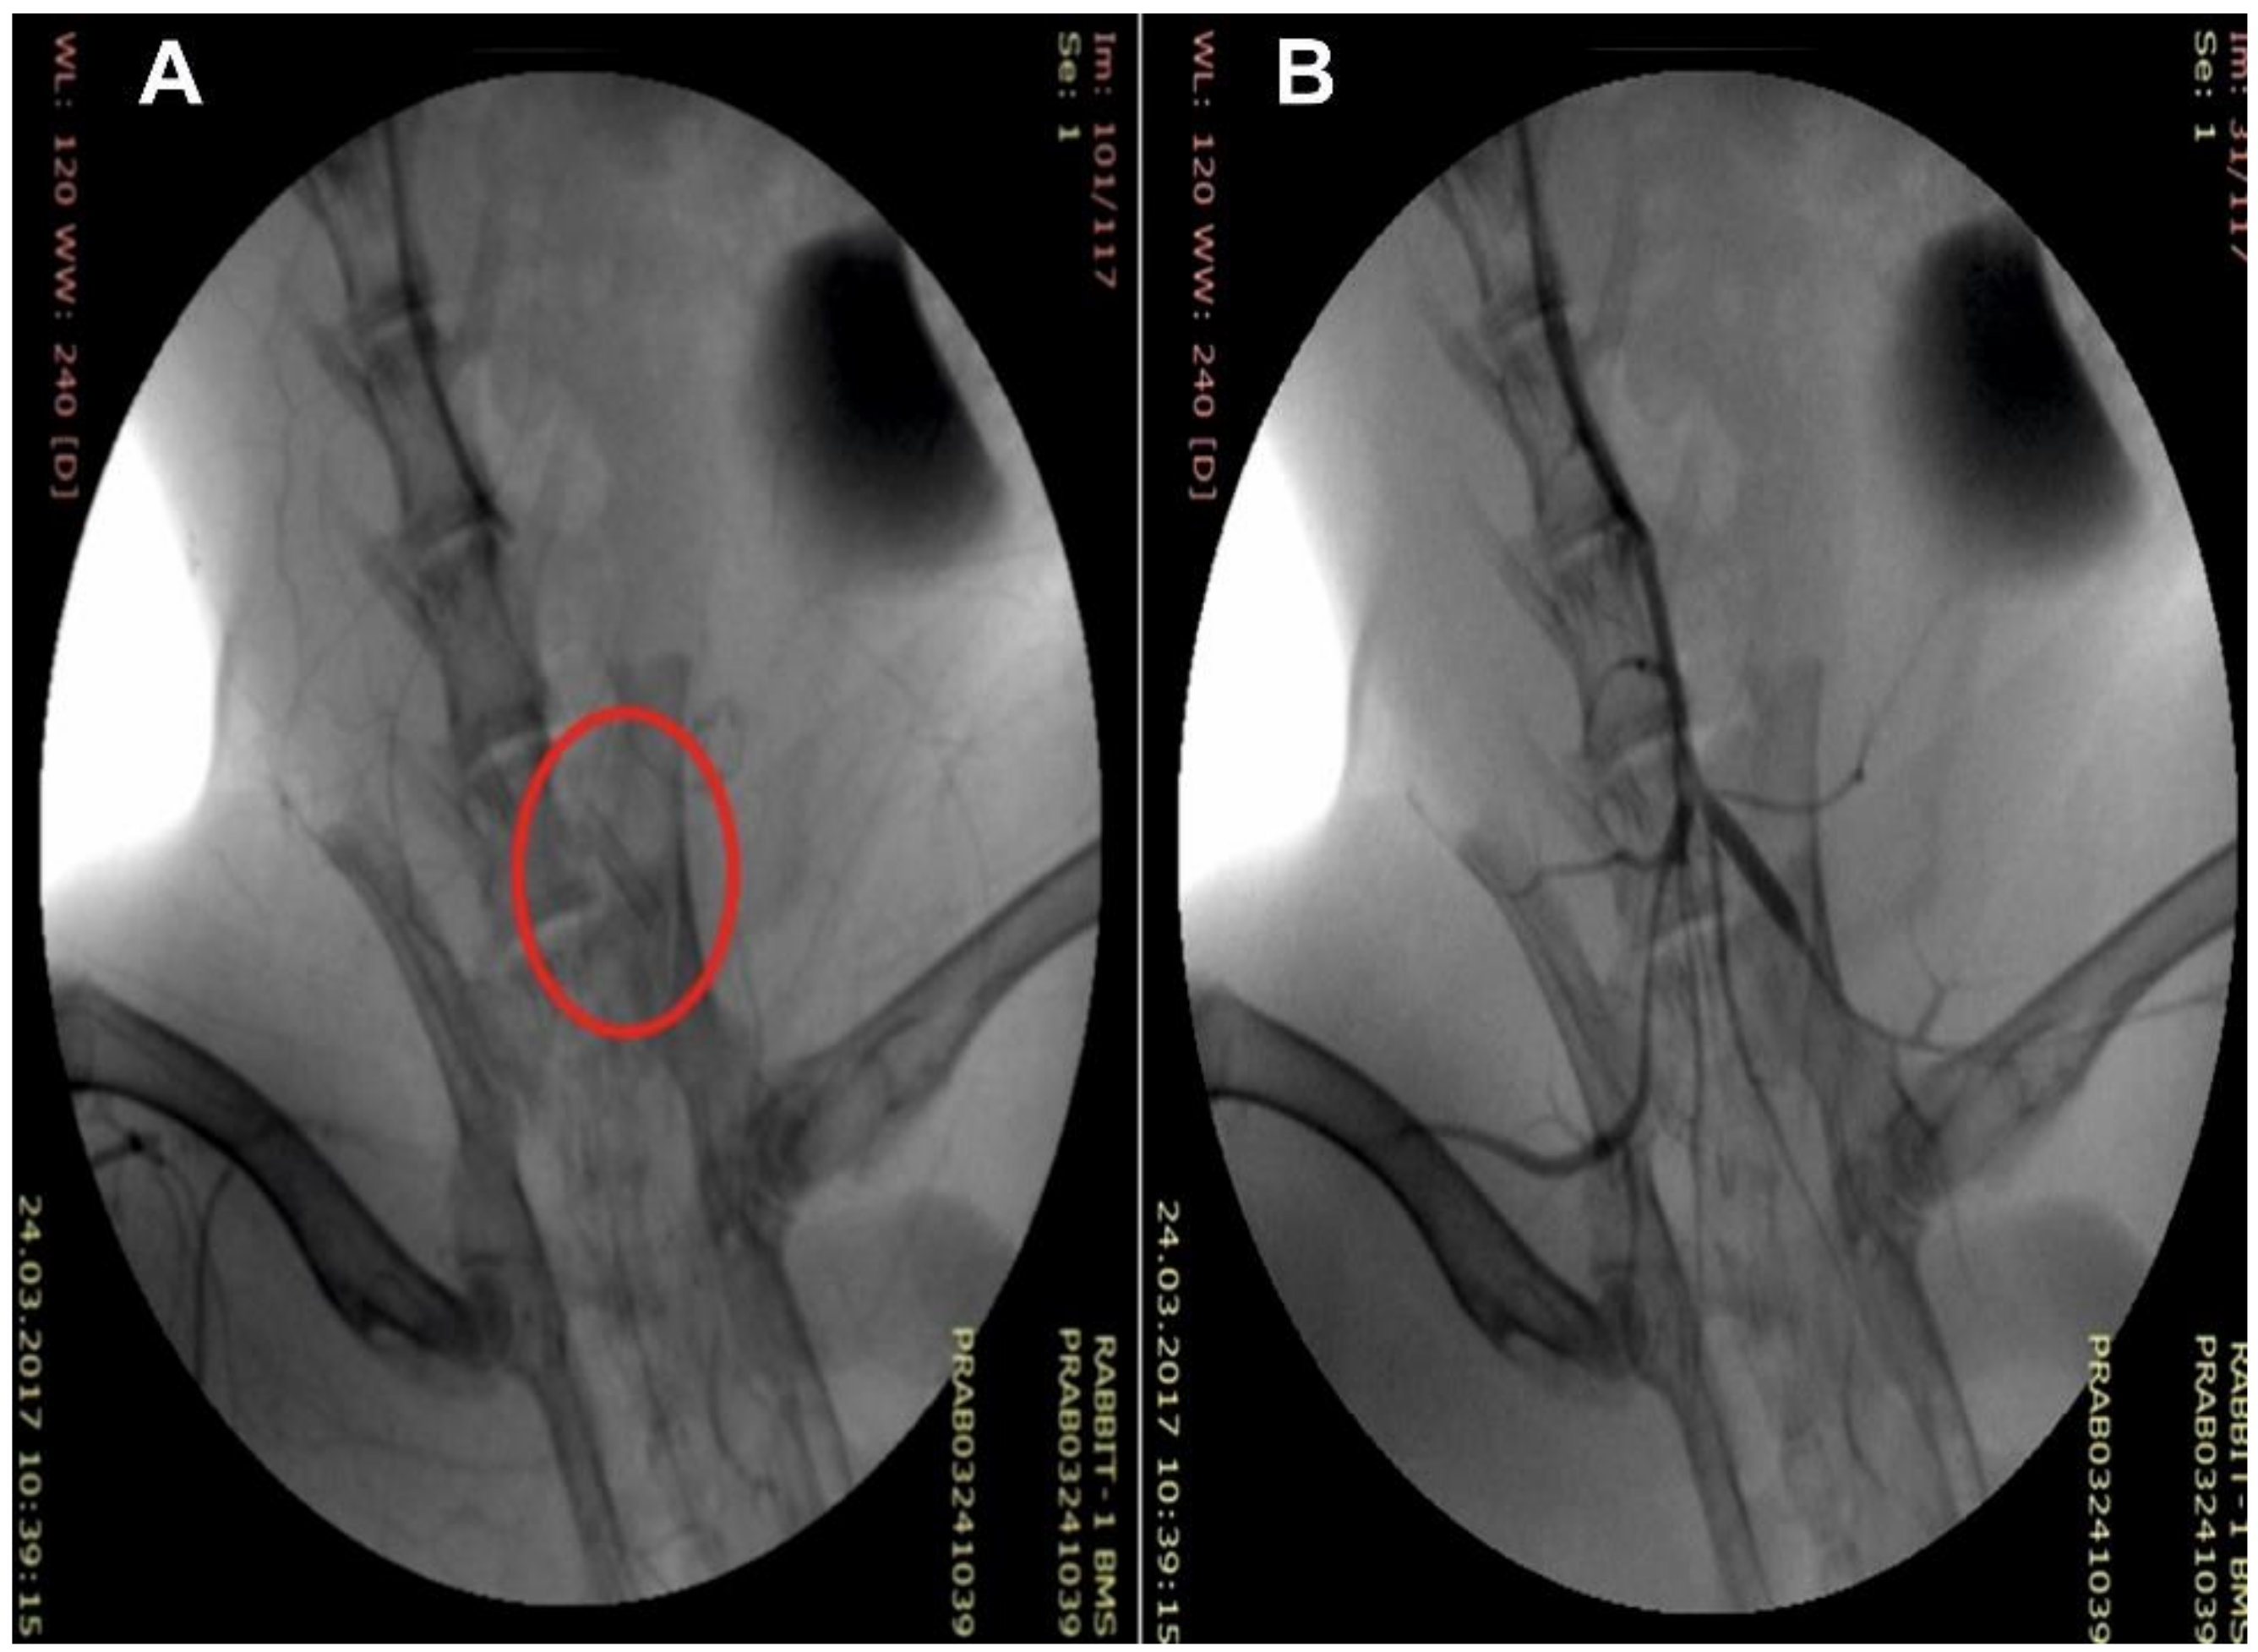

Because the coating produced by electrospinning shrinks and the region of its elastic deformation amounts to approximately 8–10% [35], the procedures described in Materials and Methods allowed for removal of the coated stent from the electrode and its shrink-fitting on the balloon (Figure 2A), providing its stability during delivery to the iliac artery and precise positioning at the target site (Figure 3). When pressing on the coating of the balloon catheter, slight deformation was observed, which did not affect the orientation of the electrospun fibers (Figure 2B,C). Stent expansion led to deformation of the covering accompanied by alignment of the fibers and small pressing of the coating inward between the stent struts (Figure 2D–F). It should be noted that folds of the material on the surface of the struts were obviously related to a small “reverse” deformation of the stent after its expansion (Figure 2D).

Figure 3. Intraoperational view of the stent with tissue engineered coating (C arm): (A) an implanted stent and (B) its angiographic control.